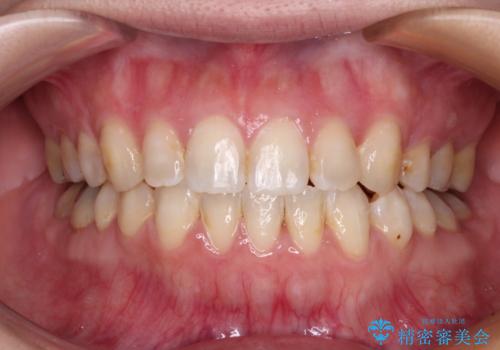

前歯の叢生をいつの間にか改善 インビザラインによる矯正治療